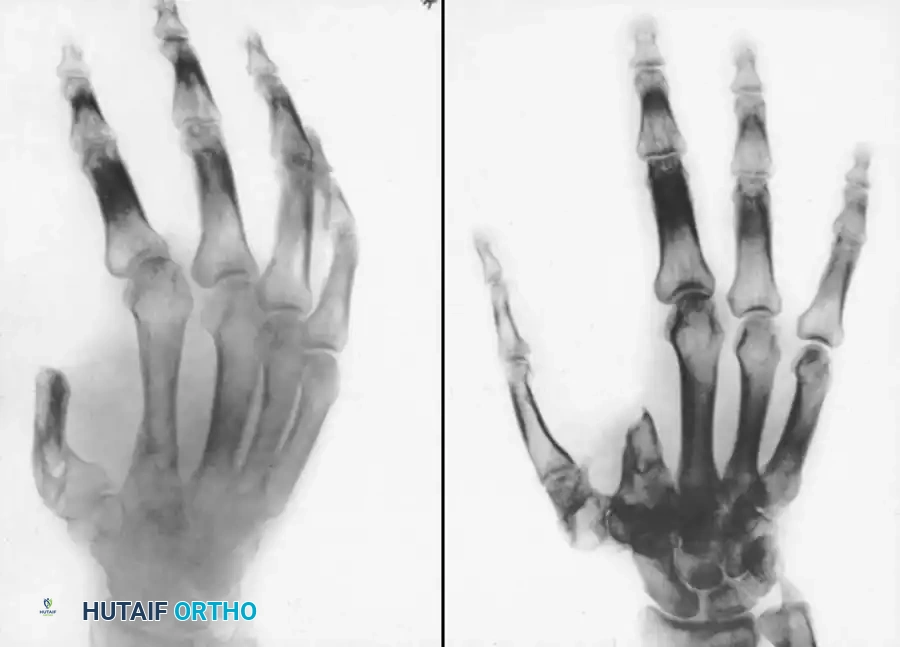

Associated Surgical & Radiographic Imaging